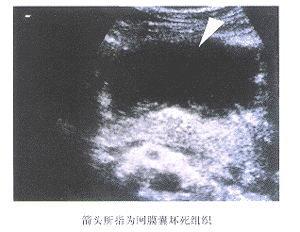

正常情况下超声难于显示网膜囊,当网膜囊积液时,胃胰间出现液性暗区,厚度可以数毫米至数厘米,形态则可是线状、条状、片状(图1);当暗区内出现片状或不规则的强回声时,往往提示坏死组织的形成,(图2),坏死组织的感染与否,有赖于B-US引导下穿刺〔2、3〕 ;假性胰腺囊肿是AP的晚期局部并发症,而本

图1 上腹部横切,Pa:胰腺,sac:网膜

图2 上腹部横切组为AP住院患者资料回顾分析,故未进行进一步分析。